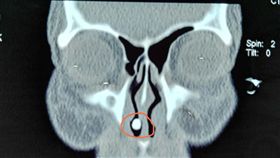

頻流鼻血誤當腫瘤 鼻子竟「長牙齒」

一名30多歲男性經常流鼻血,到耳鼻喉科就診,醫師觀察...